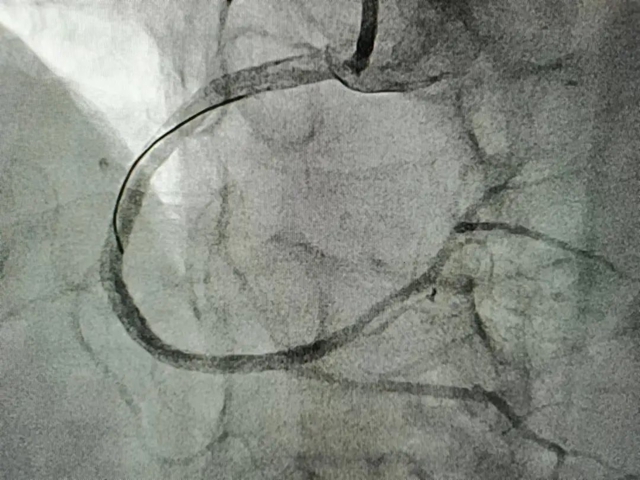

右冠脉植入支架后

一切准备就绪后,潘洪教授带领李文龙主治医师及杨廷富主管医师分两次为匡阿姨行冠状动脉介入手术,术后症状完全改善,两次手术共植入4枚支架。